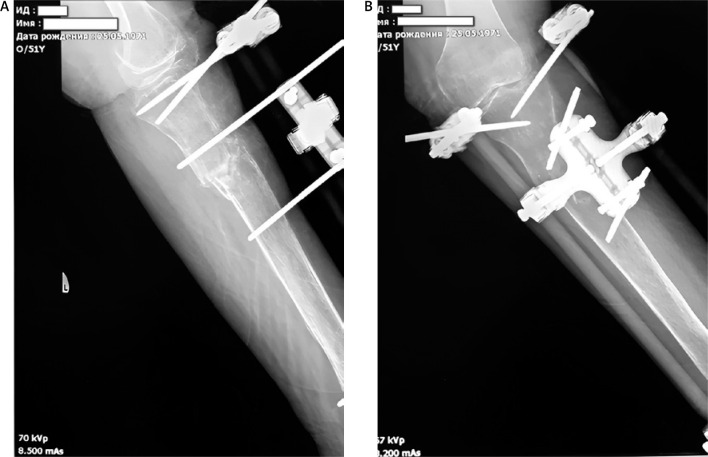

骨折延迟愈合是骨科实践中常见的并发症,尤其是骨质疏松症患者。再生医学的进步,包括间充质干细胞(MSCs)在基质血管部分,引入了新的治疗方法来解决这一挑战。本病例描述了一位患有绝经后骨质疏松症和左下肢先天性异常的患者,其胫骨近端骨折伴碎片移位。骨质疏松治疗开始,骨折使用外固定和压迫处理。尽管在8个月的时间里骨密度有所改善,但x线评估显示没有骨折愈合的证据。因此,在骨折部位进行局部给药联合针刺,然后进行一系列自体浓缩血浆(ACP)注射。3个月内,观察到骨痂形成的影像学征象,最终在开始再生治疗6个月后骨折完全愈合。尽管我们临床病例数量有限,无法对骨折愈合的主要促进因素得出明确的结论,但现有文献表明,骨折部位高浓度内源性资源的动员促进了组织再生。身体活动和辅助药物治疗进一步促进了这一过程。结合MSCs和acp衍生生长因子的再生疗法是治疗系统性骨质疏松患者骨折并发症的一种有希望的辅助方法。这种策略有可能促进骨愈合,同时可能延迟甚至避免需要更多的侵入性手术干预。

Delayed fracture union is a common complication in orthopedic practice, particularly in patients with osteoporosis. Advances in regenerative medicine, including mesenchymal stem cells (MSCs) within the stromal-vascular fraction, have introduced novel therapeutic approaches to address this challenge. This case describes a patient with postmenopausal osteoporosis and a congenital anomaly of the left lower limb who sustained a proximal tibial fracture with fragment displacement. Osteoporosis therapy was initiated, and the fracture was managed using external fixation and compression. Despite an improvement in bone mineral density over an eight-month period, radiographic assessment revealed no evidence of fracture union. Consequently, local administration of MSCs combined with needling at the fracture site was performed, followed by a series of autologous concentrated plasma (ACP) injections. Within three months, radiographic signs of bone callus formation were observed, ultimately leading to complete fracture union six months after the initiation of regenerative therapy. Although the limited number of cases in our clinic prevents definitive conclusions regarding the primary contributing factor in fracture healing, existing literature suggests that the mobilization of endogenous resources at the fracture site in high concentrations promotes tissue regeneration. This process is further facilitated by physical activity and adjunctive pharmacological treatment. Regenerative therapy integrating MSCs and ACP-derived growth factors represents a promising adjunctive approach for managing fracture complications in patients with systemic osteoporosis. This strategy has the potential to enhance bone healing while potentially delaying or even avoiding the need for more invasive surgical interventions.